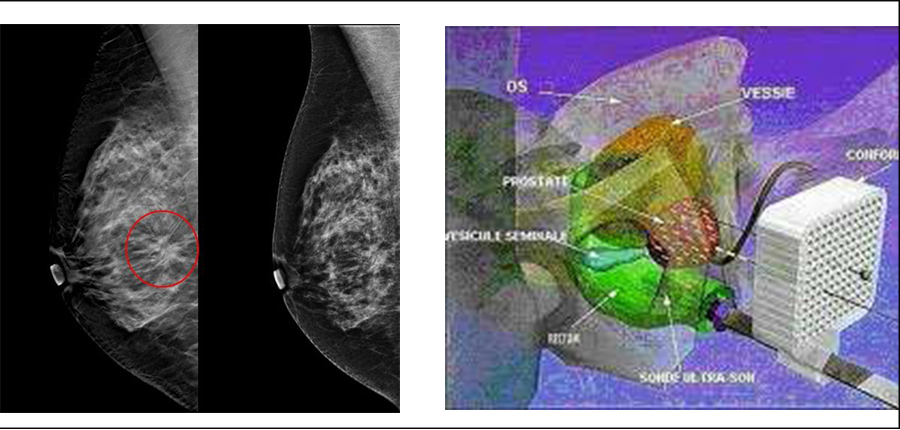

Les innovation Diagnostiques et Thérapeutiques dans le cancer du sein et de la Prostate

Dans le cadre de la formation continue post-universitaire, le Centre d'Oncologie AL AZHAR de Rabat, organise une Table Ronde le 18 Avril 2017 à l'Amphitrite Skhirat sur les actualités dans les Cancers du sein métastatiques en 2017,les pièges de la mammographie,la curiethérapie dans le cancer de la prostate ainsi que l'étude de Cas cliniques pratiques.